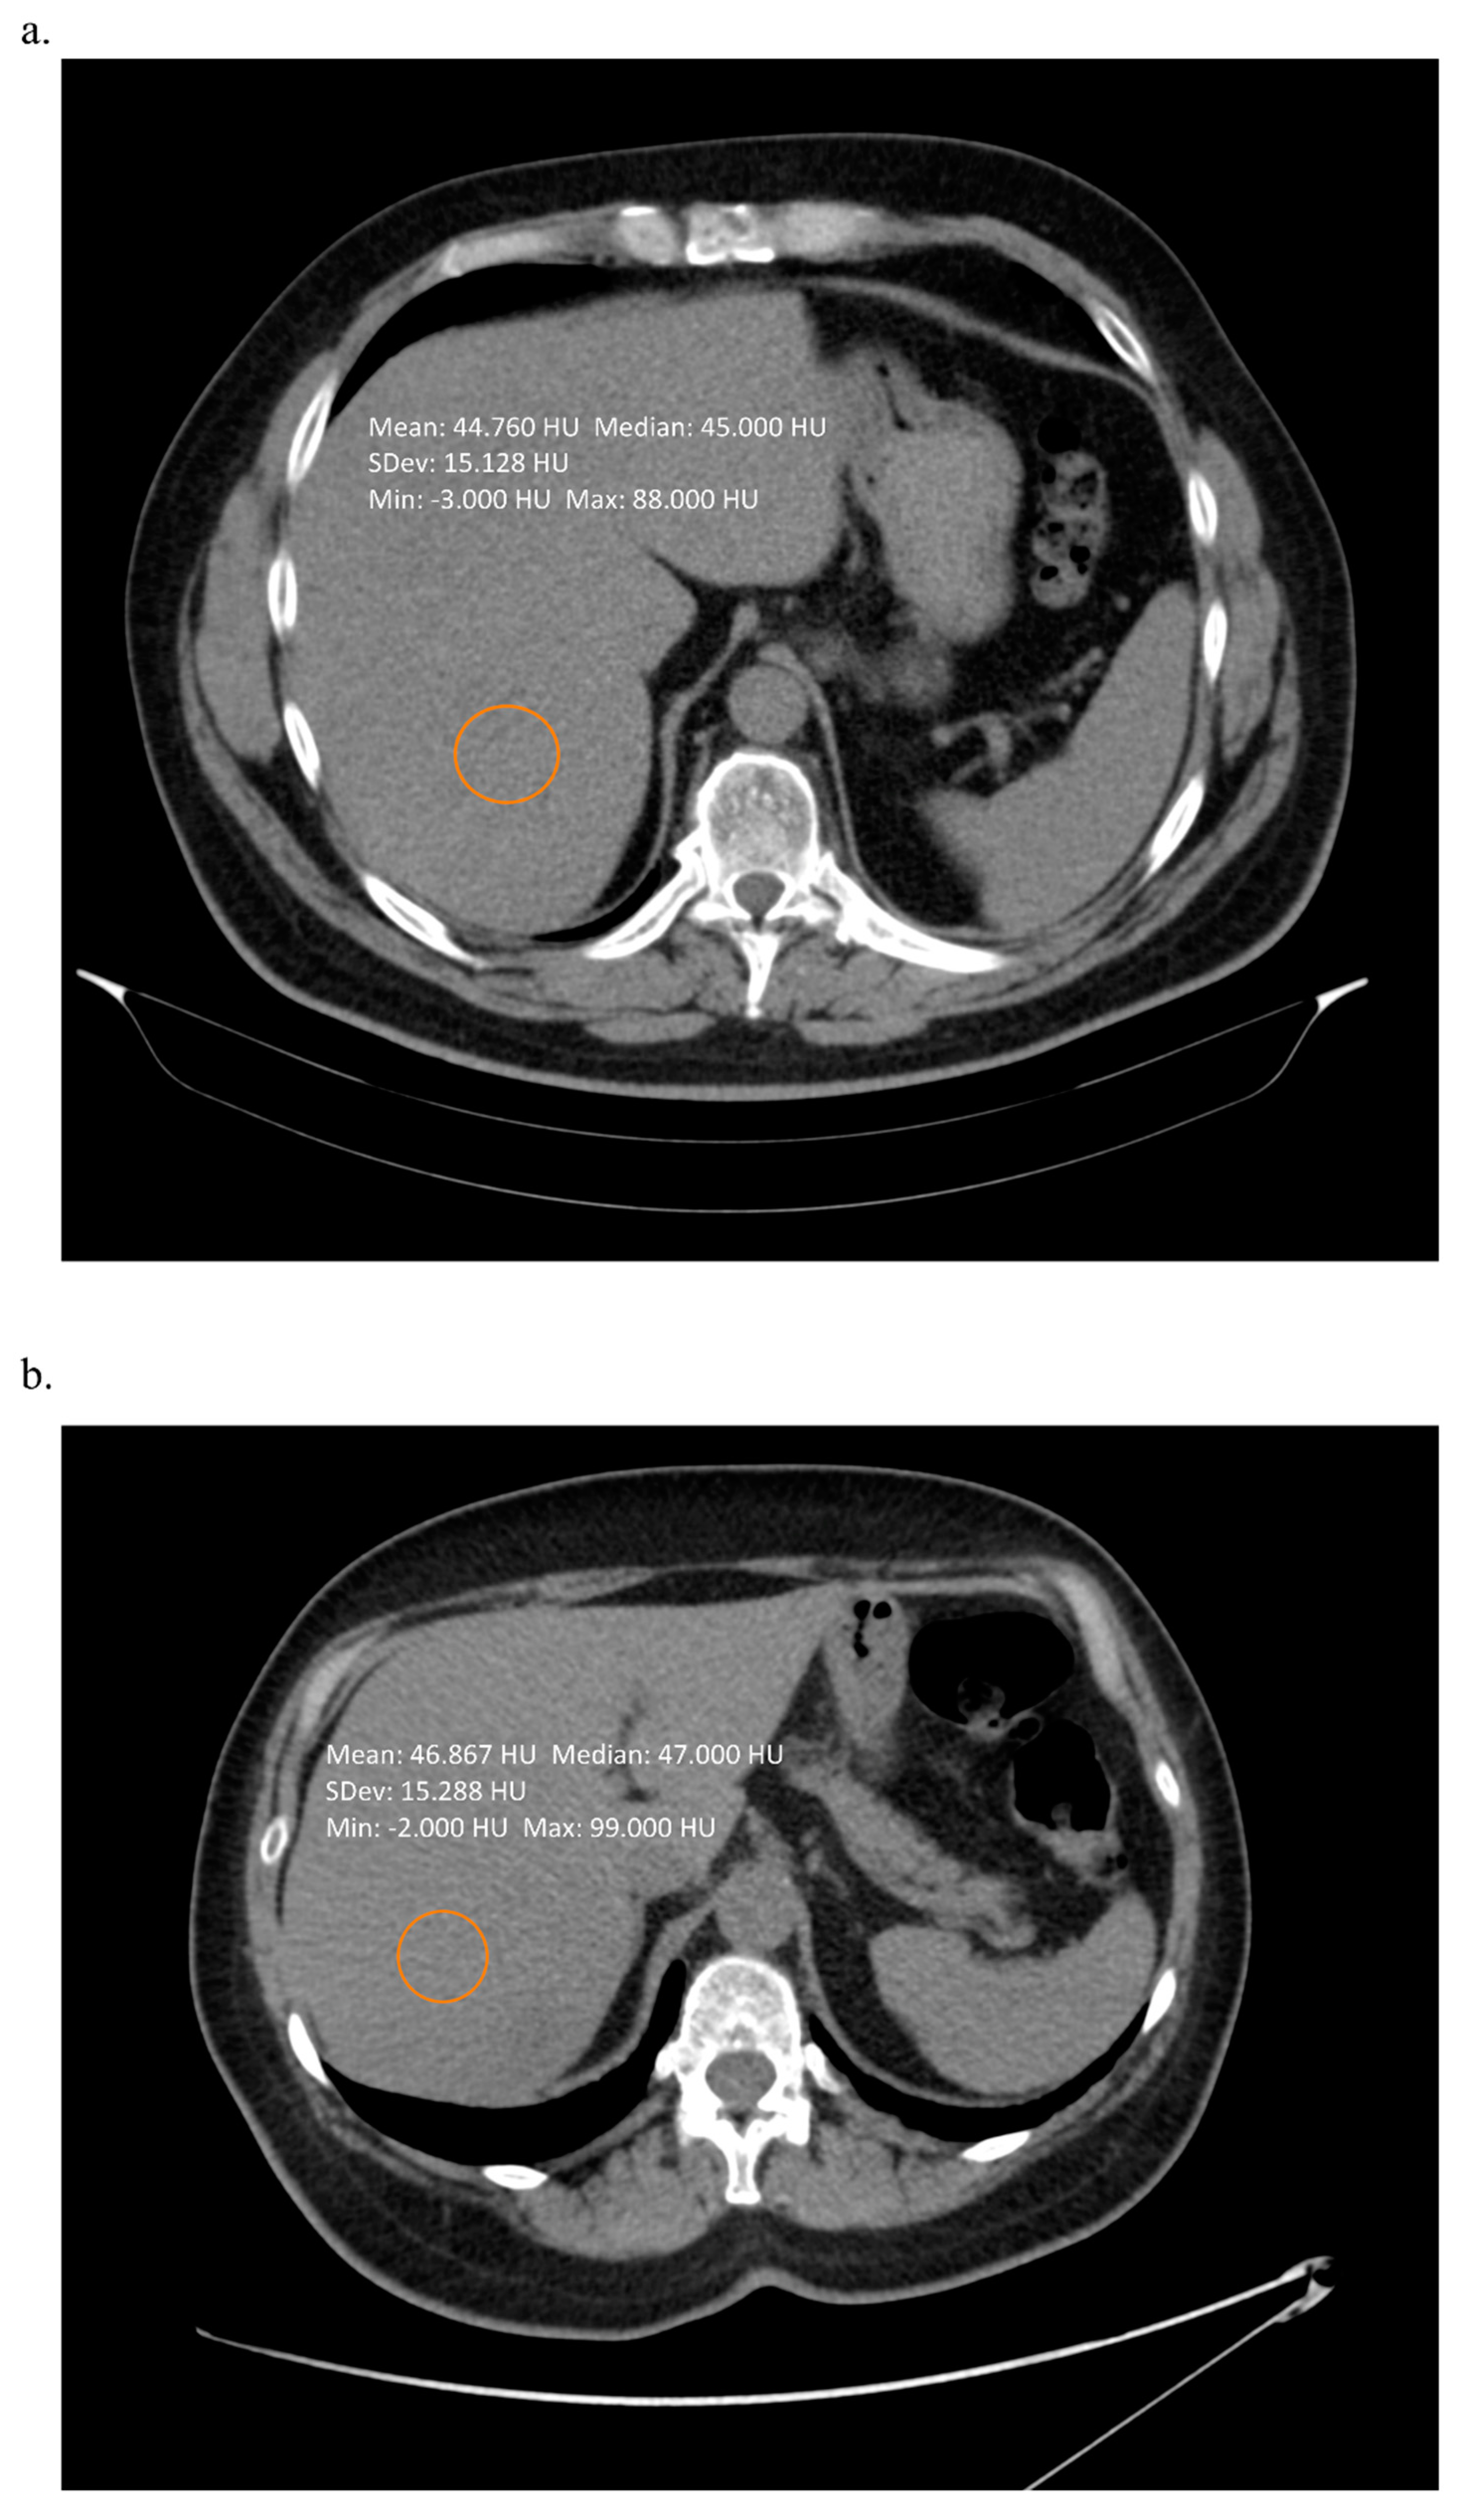

2. Techniques Using Computed Tomography